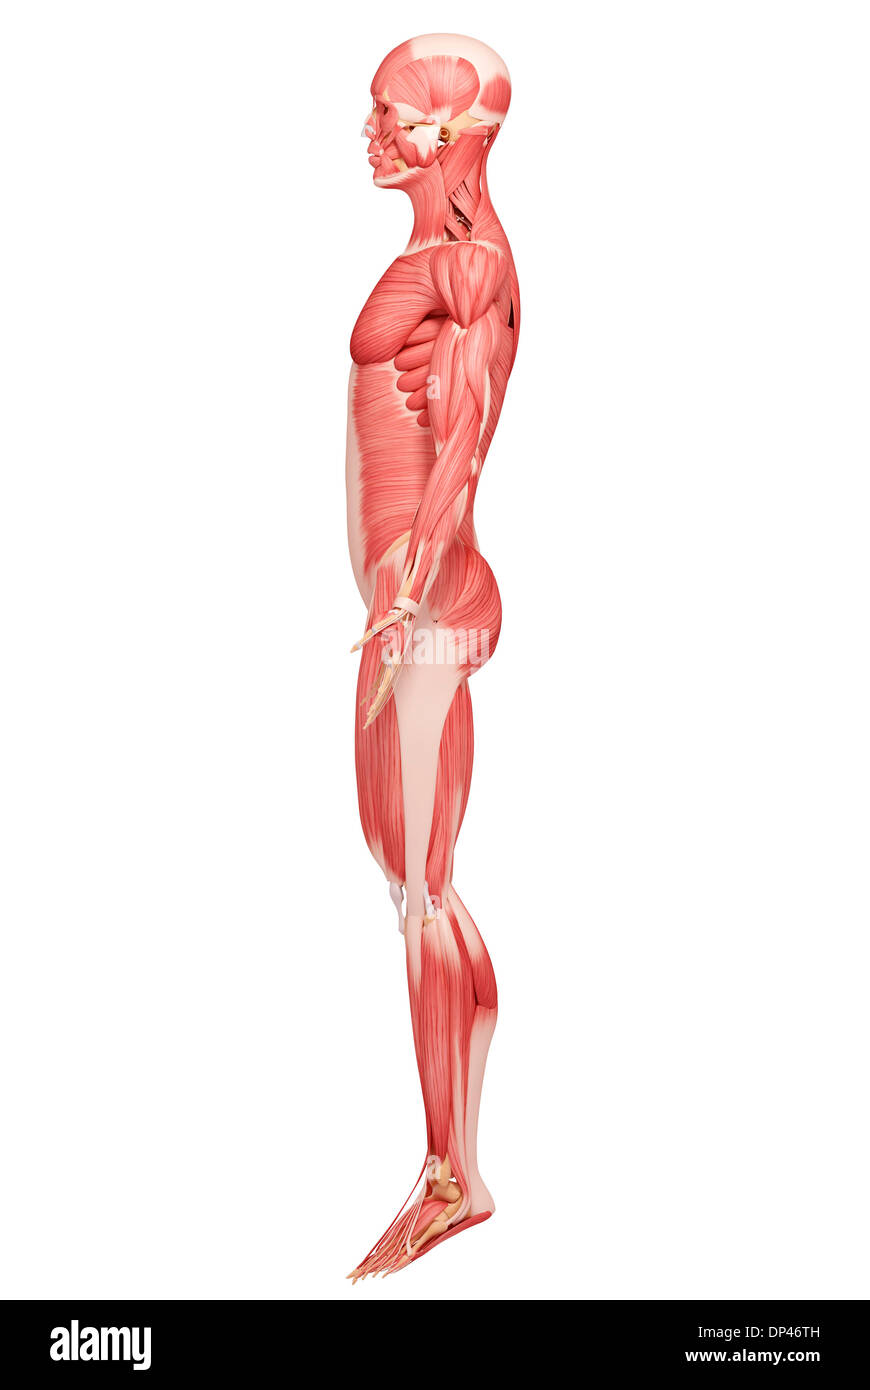

Musculature, artwork Banque D'Imageshttps://www.alamyimages.fr/image-license-details/?v=1https://www.alamyimages.fr/musculature-artwork-image65226679.html

Musculature, artwork Banque D'Imageshttps://www.alamyimages.fr/image-license-details/?v=1https://www.alamyimages.fr/musculature-artwork-image65226679.htmlRFDP3987–Musculature, artwork